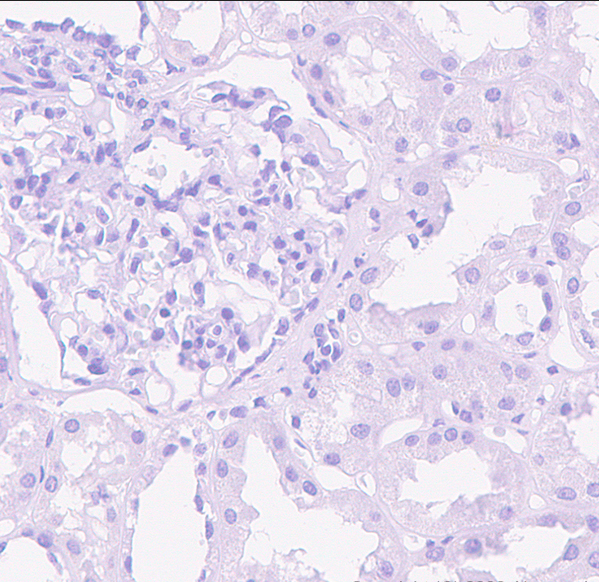

CXCL13 is a chemokine associated with B cell migration to the germinal center, produced by follicular helper T cells (TFH) originating from the germinal center. Studies have shown that in lymph nodes, CXCL13 is expressed exclusively in TFH cells and not in other T cells. Angioimmunoblastic T-cell lymphoma (AITL) is a lymphoma originating from follicular helper T cells. A key diagnostic challenge is distinguishing it from reactive hyperplasia (RH) characterized by paracortical zone proliferation and non-specific peripheral T-cell lymphoma (PTCL, NOS). CXCL13 is highly expressed in AITL (over 89%) and lowly expressed in PTCL, NOS (30%). In combination with CD10 and bcl-6, it serves as a useful marker for the diagnosis and differential diagnosis of AITL.

CXCL13 antibody reagents can specifically bind to the CXCL13 molecular antigen. Immunohistochemistry kits containing CXCL13 antibody reagents are suitable for the precise diagnosis of angioimmunoblastic T-cell lymphoma.